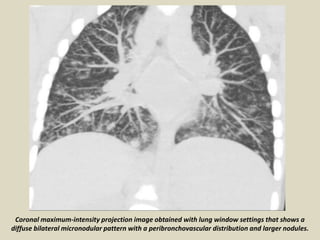

Coronal maximum-intensity projection image obtained with lung window settings that shows a

diffuse bilateral micronodular pattern with a peribronchovascular distribution and larger nodules.